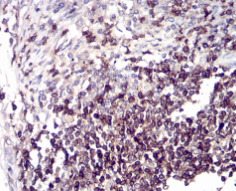

CD6 Mouse Monoclonal antibody[5A10A2]

IHC    1/200 - 1/1000